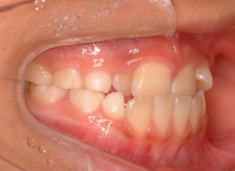

FX(フェイシャルアキシス)は85度なので東洋人の平均値に近く、下顎が前方に過剰成長するリスクは強くはありません。

しかしやはり上顎は劣成長で、下顎が優位な状態ではあります。

上下顎のギャップはありますが、顔面自体の幅径は良好な値を示していますので、スペース不足は拡大することによって解決できポテンシャルはあると考えられます。

左右の非対称もさほど強くありません。